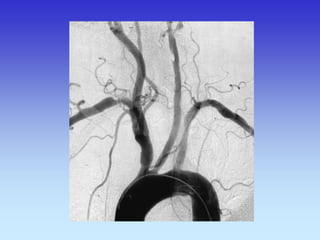

METODE PRIKAZA KRVNIH ŽILA

•UZ-DOPPLER

•DSA

•CTA

•MRA

B-mod i obojeni Doppler karotidne arterije